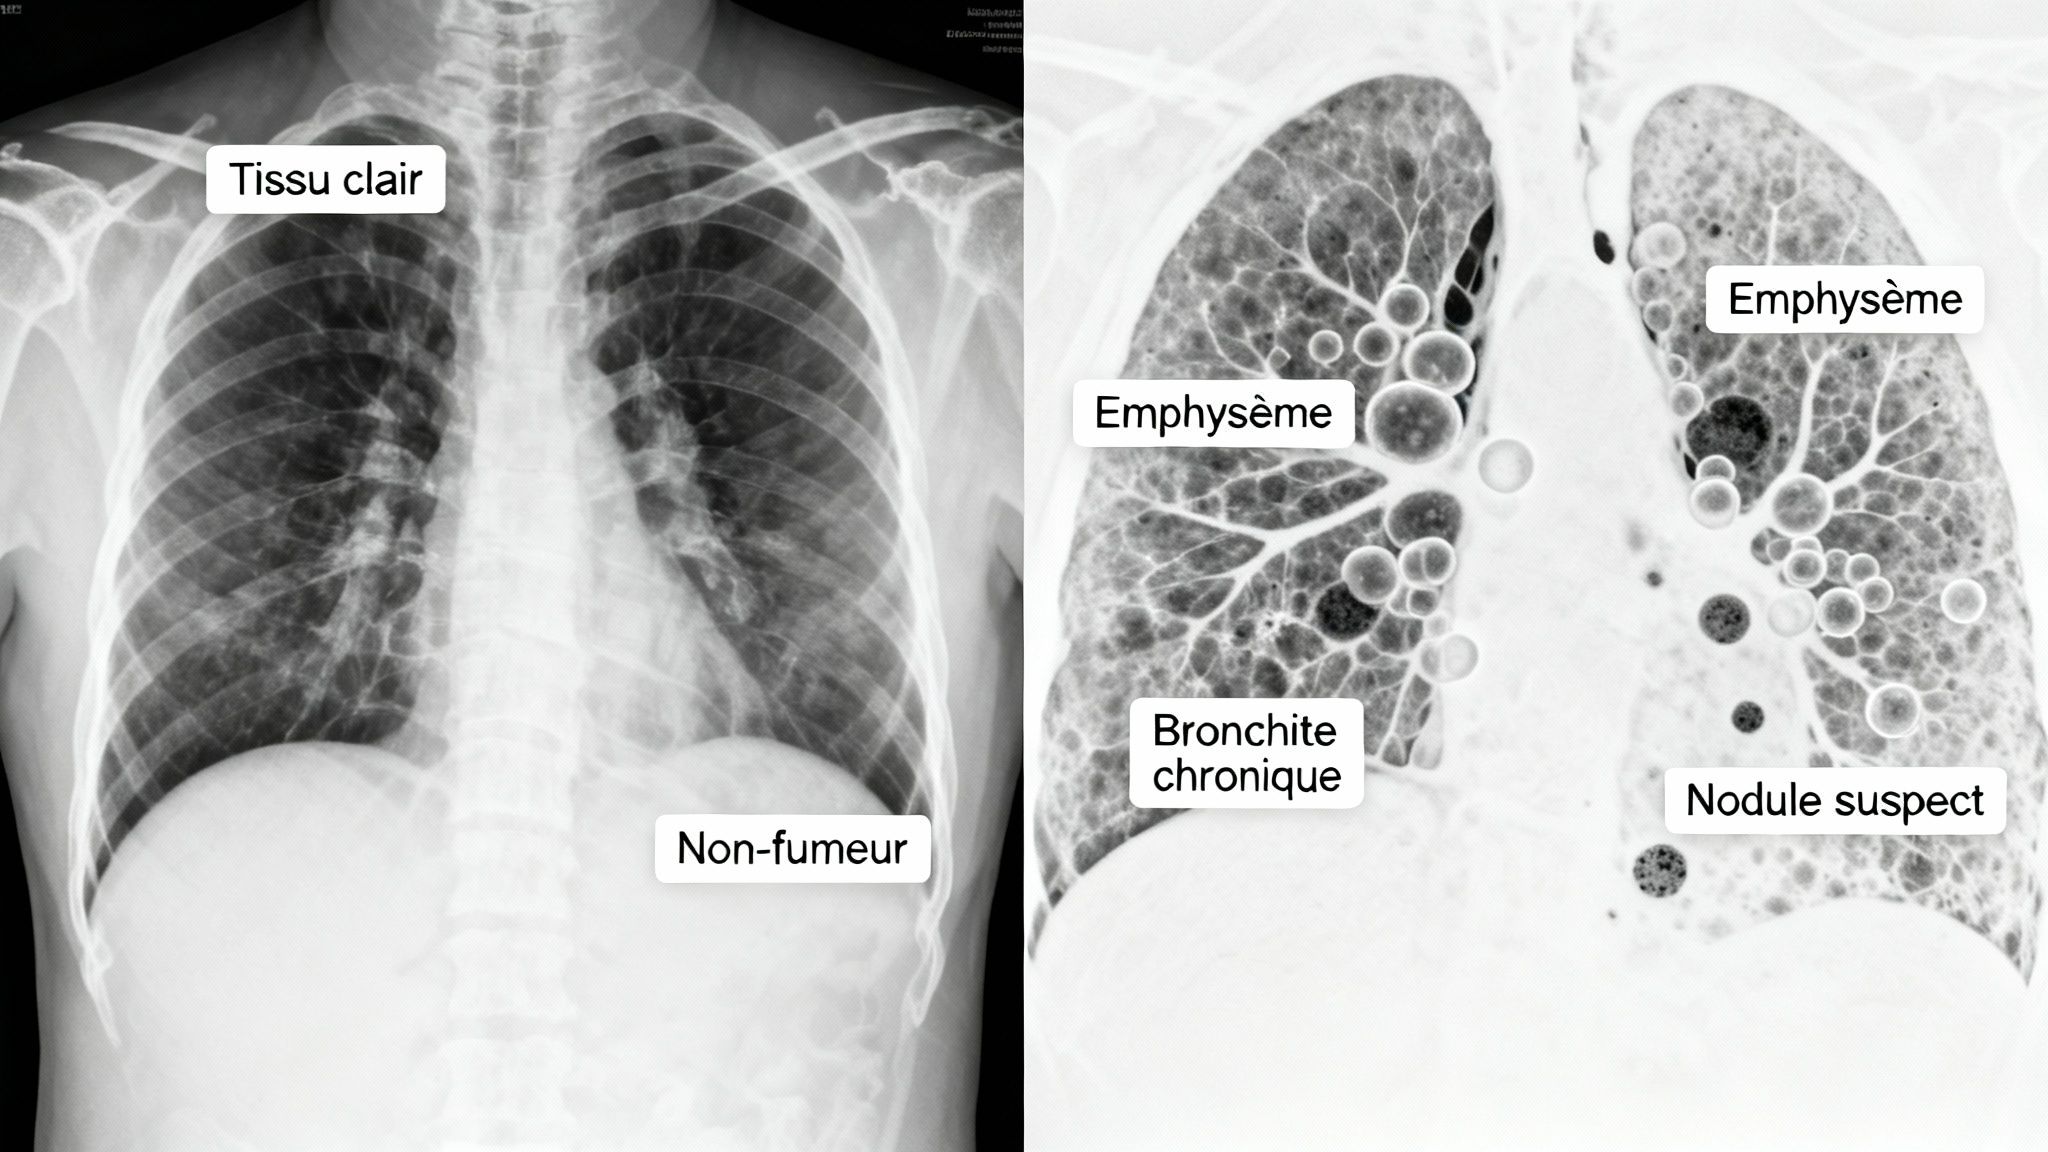

Au-delà des symptômes que l'on peut ressentir au quotidien, l'imagerie médicale met noir sur blanc les dégâts du tabac. Une simple radiographie ou un scanner du thorax, c'est un peu comme ouvrir le capot d'une voiture : même si elle roule encore, on voit tout de suite les pièces abîmées. Ces examens transforment les risques théoriques en une réalité visuelle, souvent frappante.

Chez un non-fumeur, l'image est généralement limpide. Le tissu des poumons apparaît clair, uniforme, sans la moindre trace d'inflammation ou de blocage. C'est le signe d'un moteur qui tourne à plein régime.

En revanche, chez un fumeur, le tableau est rarement aussi net. Les radiologues savent exactement quoi chercher, des indices qui trahissent des années d'exposition à la fumée.

Les signes qui ne trompent pas sur un scanner

Un scanner thoracique, bien plus détaillé qu'une radio, révèle avec une précision chirurgicale l'état des poumons d'un fumeur. Les médecins y recherchent des marqueurs bien précis, qui sont souvent les premiers signes de maladies graves.

Voici ce qu'ils repèrent le plus souvent :

- Épaississement des parois des bronches : C'est la signature typique de la bronchite chronique. L'inflammation constante épaissit les parois des voies respiratoires, ce qui réduit le passage de l'air et rend la respiration plus difficile.

- Destruction des alvéoles (emphysème) : Imaginez que les petits sacs qui permettent l'échange d'oxygène sont détruits un par un par les toxines. Sur le scanner, cela se traduit par des sortes de "bulles" noires, des zones vides où le tissu pulmonaire a tout simplement disparu.

- Présence de nodules pulmonaires : Ce sont de petites taches, souvent rondes. Bien qu'ils puissent être bénins, ils sont beaucoup plus fréquents chez les fumeurs et imposent une surveillance stricte. Ils peuvent être le premier signe d'un cancer.

Ces détails ne sont pas juste du jargon médical. Ils expliquent concrètement pourquoi un fumeur est souvent essoufflé, tousse en permanence ou attrape des infections à répétition.

L'imagerie médicale révèle ce que le corps endure en silence. On ne parle pas juste de poumons "noircis", mais d'une véritable destruction de l'architecture des poumons qui mène, petit à petit, à la perte du souffle.